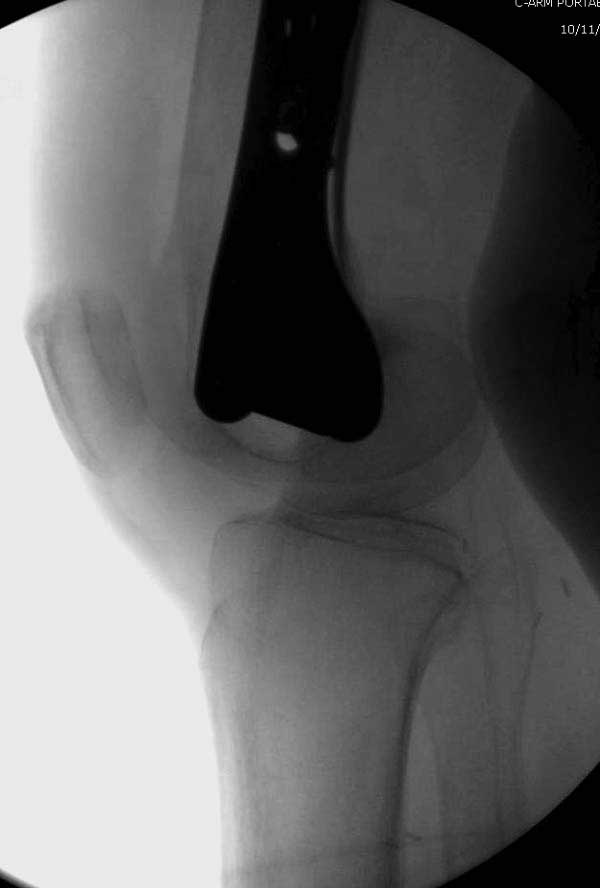

Такие “чужие осложнения” встречаются у всех и представляю банальный случай, который шаг за шагом показано как перерос в более сложный процесс... Больная 70 лет, множественные ко-морбидности, чрезвертельный перелом первоначально фиксирован Гамма 3. Осложнение в течение 6 недель, ревизия тотальной артропластикой и во время установки ножки обнаружена трещина диафиза (17), из малого доступа фиксация алло-графтом.

Обычно после чрезвертельных переломов, за исключением молодых, у пожилых остается нестабильность при движении. Часто падают и после 3х мес. в результате падения обнаружен перипротезный перелом (22-23), который зафиксирован Синтез пластиной.

Повторно поступает после двух с половиной лет, где обнаруживается перелом на второй стороне. Немного сложно, но для фиксации выбрали Antegrade InterTan Smith Nephew Nail и с момента фиксации более 3х мес.